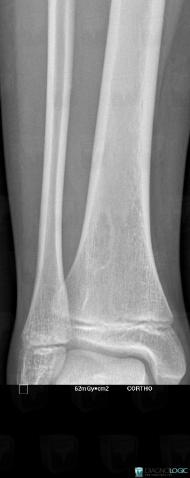

Fibrous cortical defect, Tibia - Distal part, X rays

Here is the specific information in the key image above:

- Diagnosis Fibrous cortical defect, Location(s) Tibia - Distal part, with gamuts Cortical osteolysis, Endosteal scalloping, Meta-diaphyseal osteolysis